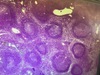

Spleen, Storage type